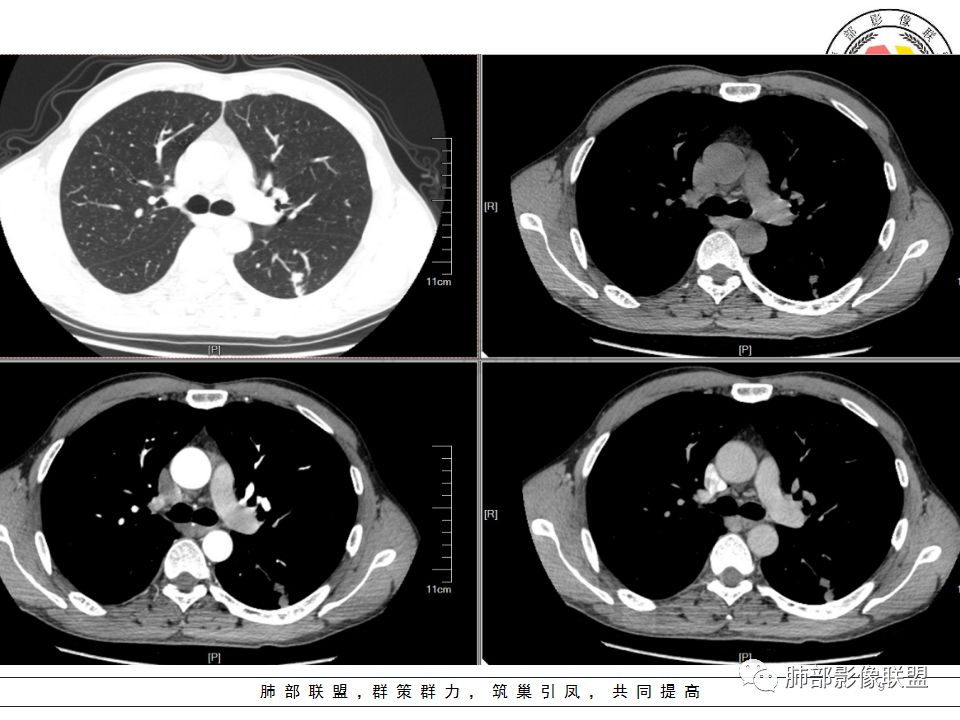

患者中年男性,因胸痛半月入院。查血常规、凝血功能、肾功能正常。有抽烟史。胸部CT:左肺下叶背段胸膜下与胸膜垂直长条形不规则病灶,支气管爬行改变,边缘欠清楚,部分层面呈葫芦样见血管集束征、周围点状卫星灶,增强无明显强化,左肺门淋巴结肿大。综合常规结核可能性大,其次小细胞肺癌。鉴别其他。

中年男性,胸痛,吸烟史。左肺下叶背段结节,边界清楚,局部见小毛刺及胸膜牵拉,部分层面成葫芦形,局部与胸膜宽基底相贴,邻近胸膜增厚。近端支气管达病灶边缘处,似略增厚。周围见少量卫星微结节及树丫。增强扫描无强化。考虑:1,结核:支持点有发病部位,邻近卫星灶及树丫,近病灶边缘支气管壁似略增厚,邻近胸膜增厚。不支持点,引流支气管壁增厚范围不够长。2,小细胞癌:支持点有局部葫芦形,似沿支气管向肺门区扩展。3,腺癌:支持点有毛刺和胸膜牵拉,当然结核也可以有这两个征象。不支持点有无强化。

病史:男,50岁,胸痛15天,无抽烟;胸膜下病灶,有可能相关;

影像:病灶不规则,形态奇特,矢状位可能看到病灶的真实形态;上面近端病灶似乎与主病灶不相连续,多病灶?内侧似乎小花小草,疑为卫星灶;胸膜下病变,与胸膜关系不密切,胸膜线状强化;强化方式渐进性,感觉不均匀,也许是伪影;病灶凹陷平直不膨隆,考虑良性。诊断:结核;鉴别:腺癌(近胸膜端三个胸膜反应凹,偏上部层面毛刺不能除外,但其他地方没有,整体收缩力还比较弱,无钙化,考虑没有形成钙化和纤维化。